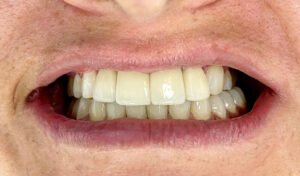

Decidí recuperar mi sonrisa y fui a la clínica dental donde me atendió la Dra. Laura Zárate. Me explico paso a paso como sería el procedimiento. Resolvió todas mis dudas y me dio la confianza para iniciar el tratamiento.

Hoy, gracias a mi prótesis híbrida, puedo reír, comer y hablar con total naturalidad. Recuperé mi sonrisa, mi confianza, mi alegría. Hoy puedo decir que recupere mi calidad de vida